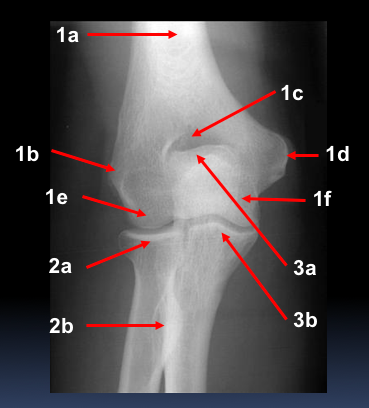

What are the labels?

1a - distal shaft

1b - lateral epicondyle

1c - olecranon fossa

1d - medial epicondyle

1e - capitulum

1f - trochlea

2a - radial head

2b - radial tuberosity

3a - olecranon

3b - coronoid process